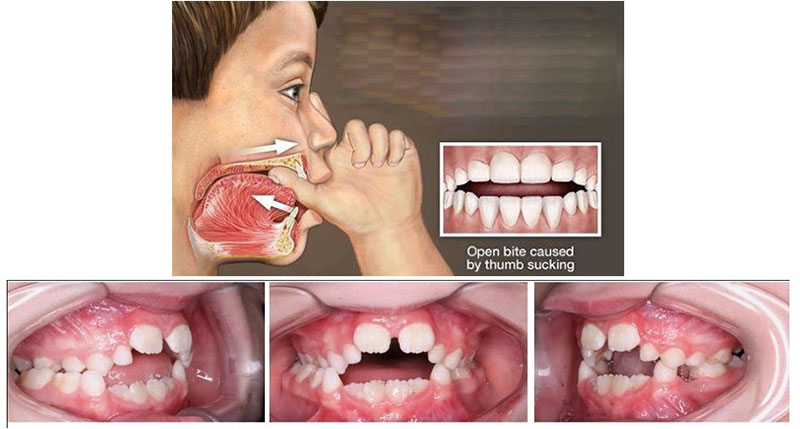

۱- مکیدن انگشت:

مکیدن انگشت یا پستانک در دوران نوزادی و کودکی می تواند یک عادت ناخوشایند با تاثیرات طولانی مدت بر ساختار فک و دندان ها باشد. این عادت ممکن است باعث ایجاد فشار های نامناسب بر روی فک و دندان ها شود و در نتیجه، اورجت و جلو زدگی دندان های فک بالا را ایجاد کند. نظارت و مشاوره از سوی والدین و دندانپزشک در دوران کودکی می تواند در شناسایی این عادت ها و اعمال تدابیر مناسب برای جلوگیری از آنها کمک کند. در برخی موارد، ارتودنتیست ممکن است راهکار های درمانی ارائه دهد تا بهبود وضعیت دندان ها و فک ها صورت گیرد و از بروز اورجت جلوگیری شود.